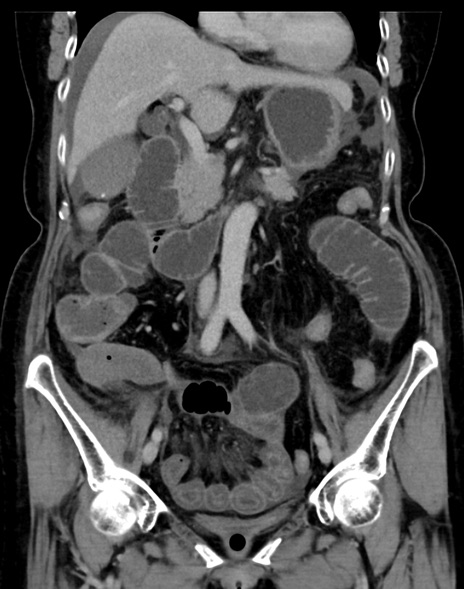

症例13 CT(冠状断像)1日半後